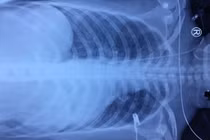

Người bệnh được chuyển đến Bệnh viện đa khoa tỉnh Phú Thọ trong tình trạng khó thở nhiều, da xanh nhợt, mạch khó bắt, huyết áp 90/60mmHg, vết thương thành ngực trái ngang mức khoang liên sườn 5, kích thước 2cm, tiếng tim mờ. Siêu âm cấp cứu tại giường có nhiều dịch máu trong màng tim và màng phổi trái, người bệnh được tiến hành các biện pháp hồi sức và được chỉ định phẫu thuật cấp cứu.

Trong phẫu thuật, các bác sĩ thấy trong khoang màng tim có rất nhiều máu đỏ tươi, khoang màng phổi có 400ml dịch máu đỏ, vết thương rách màng tim thấu vào cơ tim ngay sát động mạch vành phải đã được máu cục bịt lại không còn chảy máu nữa. Các bác sĩ đã lấy máu cục và khâu kín vết thương cơ tim.